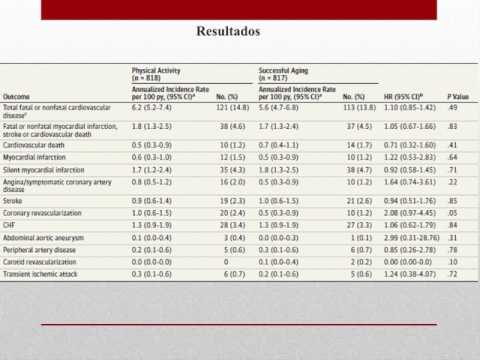

Actividad fisica y mortalidad en pacientes con enfermedad coronaria cronica. Dra. Carolina Pappalettere. Residencia de Cardiología. Hospital C. Argerich. Buenos Aires